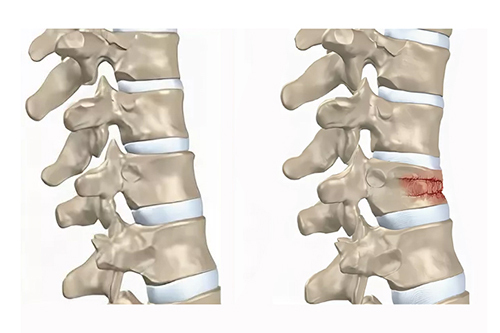

Перелом l2 l3

Перелом l2 l3 111 фото